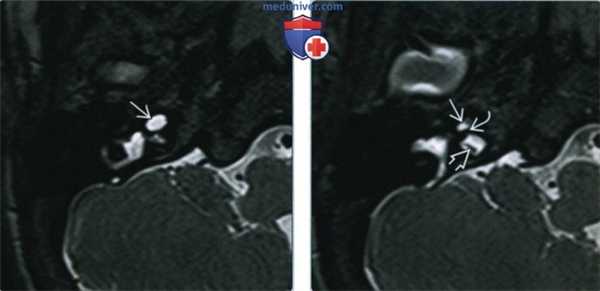

Рис. 2. МРТ, аксиальная проекция. Справа — полное отсутствие жидкости в улитке (короткая стрелка), слева — частичное (длинная стрелка).

Один пациент, по данным КТ височных костей, имел двустороннюю облитерацию лабиринта, включая улитки с двух сторон, с большей выраженностью патологических изменений справа. На МРТ было выявлено уменьшение количества жидкости в улитке справа, слева количество жидкости в улитке соответствовало норме (рис. 1, 2).